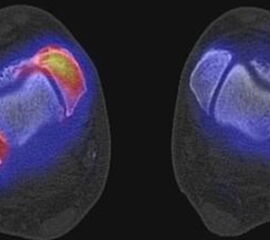

Abbildung 1.8.a und b: Akute Arthritis bei bekannter Gicht in beiden OSG: links die Früh-/Weichteilphase; rechts die Mineralisations­phase. Deutliche, entzündlich bedingte Mehranreicherungen in der Früh-/Weichteilphase. In der Mineralisation­sphase erkennt man die entzündliche Mitreaktion der subchondralen Gelenkabschnitte.

Zum Lesen der Bildbeschreibung und zur Vollansicht bitte das Bild anklicken. Bild: H. C. Rischke

Abbildung 1.8.c - e: Akute Arthritis in beiden OSG, rechts > links. Im SPECT/CT erkennt man die Mitreaktion der subchondralen Gelenkabschnitte. Die Arthritis ist so akut, dass (noch) keine ossären morphologischen Veränderungen im CT abgrenzbar sind.

Zum Lesen der Bildbeschreibung und zur Vollansicht bitte die Bilder anklicken. Bilder: H. C. Rischke